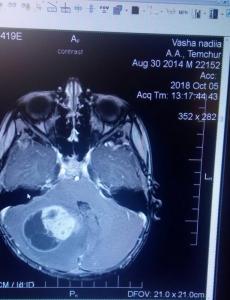

У чотирирічного Артема Темчура виявили пухлину головного мозку. Тож зараз потрібні кошти на термінову операцію.

– П'ятого жовтня чотирирічному Артему, нашому синові, зробили МРТ головного мозку. Дослідження виявило наявність значної пухлини. Дитину береться оперувати клініка в Туреччині. Втім, операція потрібна негайно: рахунок йде на дні! Вартість операції та післяопераційної реабілітації складає від 10 до 15 тисяч доларів. Тож благаємо людей допомогти нашій дитині!